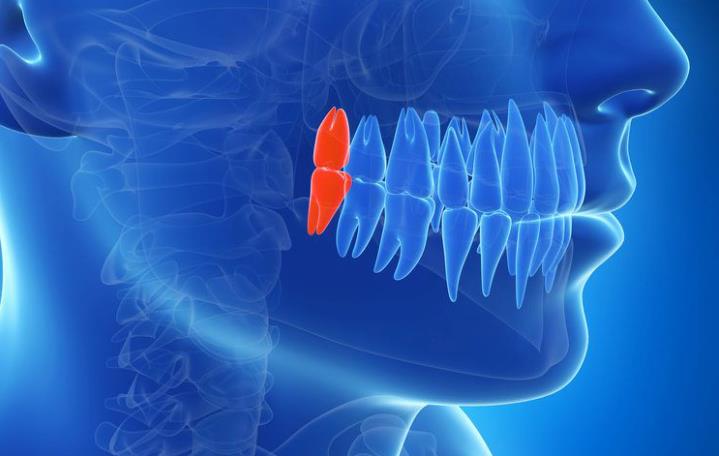

Ne razvijaju svi ljudi sva četiri umnjaka. Neko nema nijedan, neko ima samo jedan ili dva, a retki su slučajevi kada se razviju svi, ali nikada ne izniknu. Takvi zubi ostaju zarobljeni u kosti i nazivaju se impaktirani umnjaci.

Glavni problem kod umnjaka je nedostatak prostora u vilici. Savremeni način ishrane i evolutivne promene dovele su do toga da vilice budu nešto manje nego kod naših predaka. Kada treći molari pokušaju da niknu, često nemaju dovoljno mesta, pa rastu pod uglom, guraju susedni zub ili ostaju delimično prekriveni desnima.

Poluiznikli, odnosno poluimpaktirani umnjaci, posebno su skloni upalama. Deo zuba je vidljiv u usnoj duplji, dok je drugi deo i dalje prekriven mekim tkivom. U tom prostoru lako se zadržavaju ostaci hrane i bakterije, što može izazvati bol, crvenilo i otok. Ako se problem ponavlja, stomatolog će razmotriti vađenje kao trajno rešenje.

Odluka o vađenju ne donosi se napamet. Stomatolog najpre procenjuje položaj zuba, stanje okolnih tkiva i opšte zdravlje pacijenta. Rendgenski snimak vilice daje jasnu sliku o tome da li zub ima prostora za pravilan rast ili predstavlja rizik za susedne zube.

- impaktirani umnjaci zarobljeni u kosti

- nagnuti zubi koji ugrožavaju sedmicu